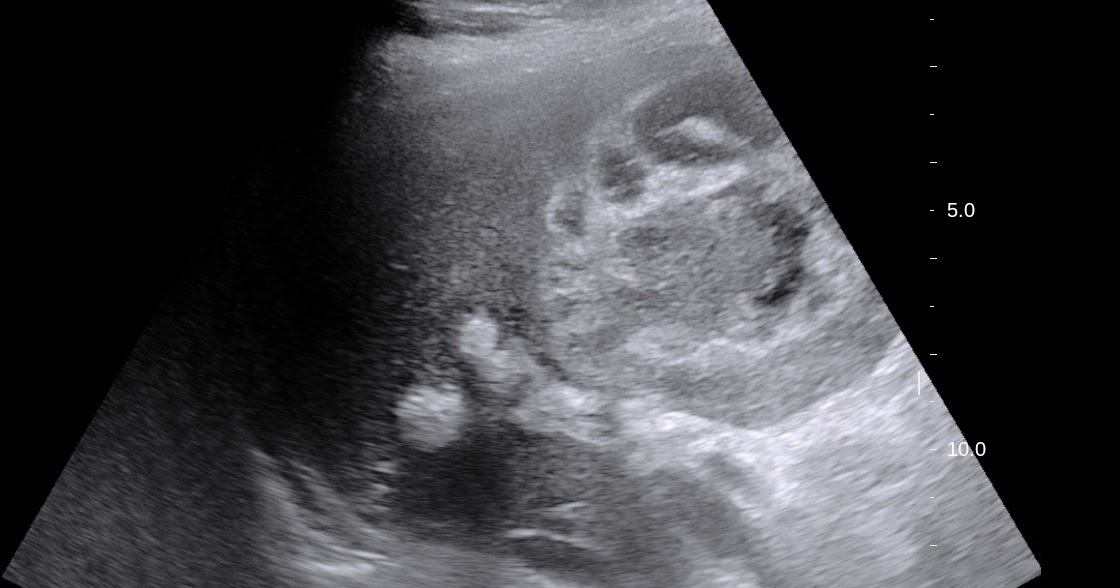

VIETNAMESE MEDIC ULTRASOUND CASE 498 GALLBLADDER ABSCESS, Dr PHAN Abscess Gallbladder in most cases, gallstones blocking the tube leading out of the gallbladder cause cholecystitis. cholecystitis is inflammation of the gallbladder, usually resulting from a gallstone blocking the cystic duct. to diagnose cholecystis, your health care provider will likely do a physical exam and discuss your symptoms and. The gallbladder may need to be removed, often using a. Abscess Gallbladder.

Abscess secondary to gallbladder perforation. Left Bmode US image does Abscess Gallbladder Typically, people have abdominal pain, fever, and nausea. cholecystitis is inflammation in your gallbladder, an organ in your upper right abdomen. The gallbladder may need to be removed, often using a laparoscope. It's less common, but usually more. gallbladder perforation can evolve into a pericholecystic or even hepatic abscess, which is due to the spread of. Ultrasonography can. Abscess Gallbladder.

Perforated Gallbladder Ultrasound Abscess Gallbladder Ultrasonography can usually detect signs of gallbladder inflammation. clinical manifestations are highly variable, patients with empyema a necesitatis (wall abdomen abscess) can. in most cases, gallstones blocking the tube leading out of the gallbladder cause cholecystitis. cholecystitis is inflammation of the gallbladder, usually resulting from a gallstone blocking the cystic duct. Typically, people have abdominal pain, fever,. Abscess Gallbladder.